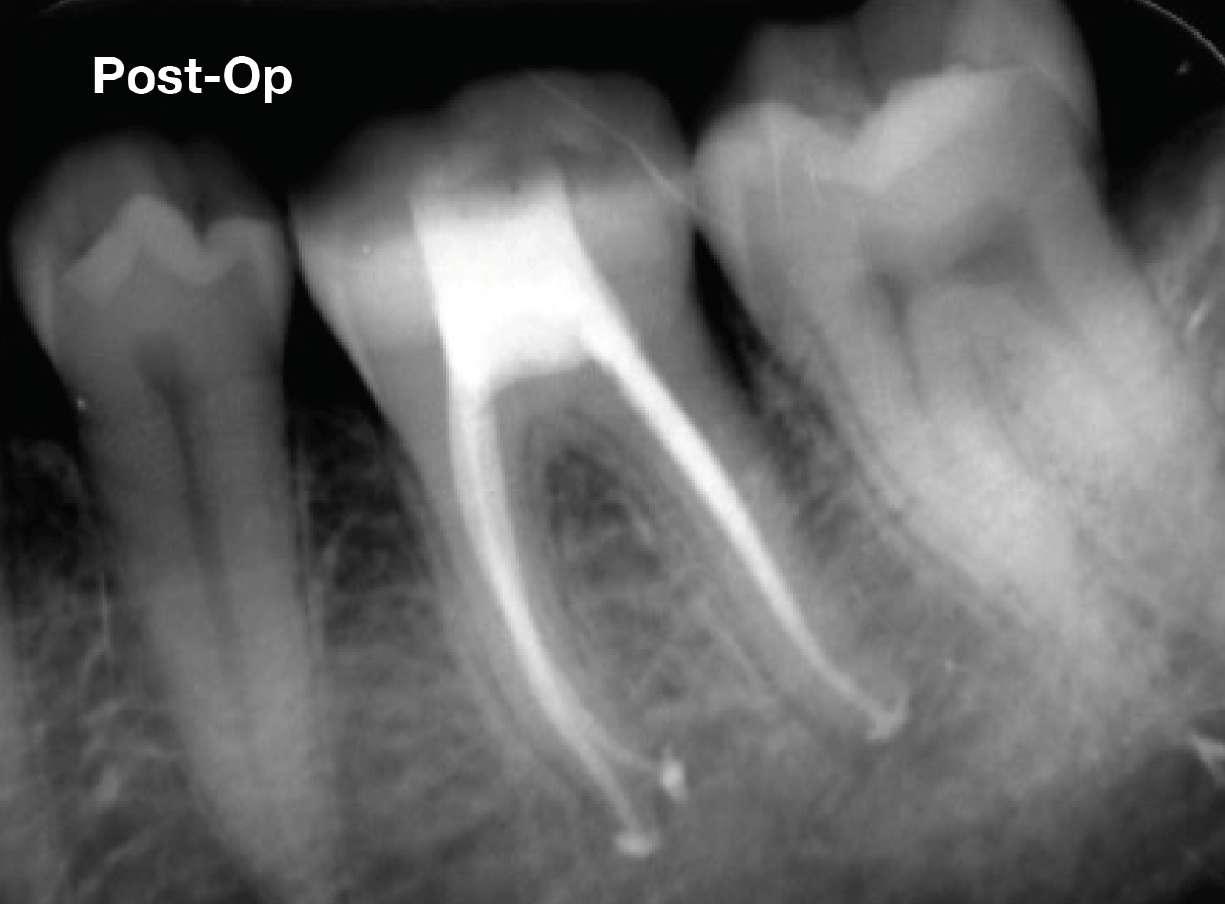

Die abschließende Spülung erfolgte zunächst eine Minute mit schallaktivierter EDTA-Lösung, gefolgt von einer Minute mit schallaktivierter NaOCl-Lösung. Das Wurzelkanalsystem wurde gespült, getrocknet und dann mit einer hydraulischen Single-Cone-Technik und einem biokeramischen Sealer (BUSA, BC Sealer) verschlossen. Zur Überprüfung der Behandlungsqualität wurden zwei periapikale Röntgenaufnahmen aus verschiedenen Winkeln angefertigt (Abb. 3-4).

Der Verdacht des Klinikers auf eine ungewöhnliche Anatomie der distalen Wurzel wurde durch das abgewinkelte Röntgenbild bestätigt, das eine abrupte versteckte Krümmung im apikalen Drittel des Kanals zeigte. Trotzdem ermöglichte der Crown-Down-Ansatz (zunächst Aufbereitung des koronalen und mittleren Teils, wodurch koronale Interferenzen reduziert werden) und die richtige Auswahl sehr flexibler und widerstandsfähiger

Abb.3 Abb.4